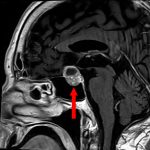

694

'25年11月

90代

頭蓋咽頭腫

頭蓋内腫瘍摘出術

No.’25_96 手術前1

No.’25_96 手術前2